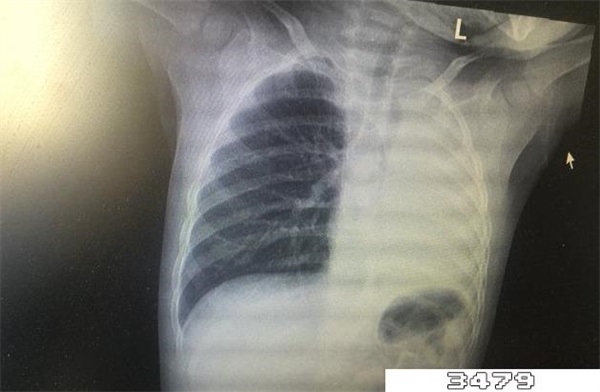

肺部变白说明肺部存在异常病变,一般由于炎症感染造成的,比如细菌感染、病毒感染和肺纤维化,也有可能是肺水肿和积液,还有可能是肿瘤引起的。此外,比较特殊的疾病比如新型冠状病毒肺炎也有可能造成肺部白化的情况。

如果是轻度肺炎引起的肺部变白,一种通过积极抗炎治疗后炎症会消退,肺部能够恢复健康。如果是比较严重的肺炎或者是肺间质纤维化引起的肺部变白,通常会伴有呼吸困难的症状,通过治疗后症状会相应减轻,但一般无法完全恢复。

严重肺炎导致肺部变白时,部分患者可以通过正确的治疗、高级生命支持、稳定内环境从而达到临床治愈,但如果患者没有进行积极治疗,或是情况过于严重,则有可能无法达到临床治愈的目的。